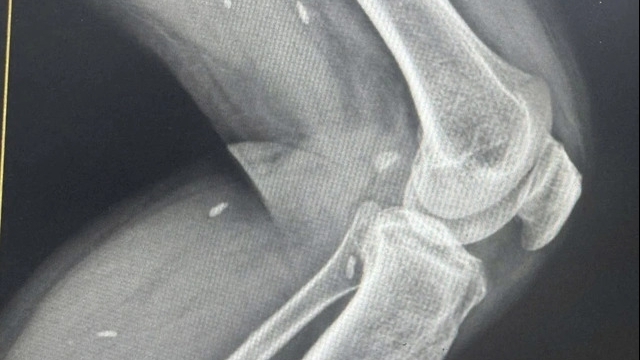

Tại bệnh viện, bệnh nhi được sát khuẩn, chuyển phẫu thuật làm sạch vết thương, dùng thuốc giảm đau, chống sốc.

Bác sĩ xác định: Bệnh nhi bị bỏng ở mức độ II, III nếu sau khi bị bỏng đến bệnh viện xử lý vết thương ngay thì thời gian phục hồi sẽ nhanh chóng, tránh các biến chứng nguy hiểm. Nhưng do không được điều trị đúng cách, bệnh nhi hiện tại bị nhiễm trùng nặng hai bàn chân, nguy cơ nhiễm trùng huyết và có thể nguy hiểm đến tính mạng bất cứ lúc nào.